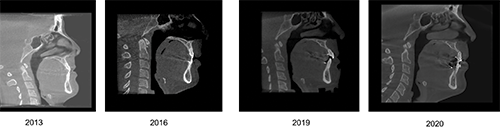

From a cephalometric perspective, the damage is difficult to visualize. Alveolar bone dehiscence and fenestration is impossible to accurately diagnose with cephalograms because of the wide focal width causing superimposition of structures. However, cone-beam computed tomography (CBCT) can quantify the damage on a slice-by-slice basis (Fig. 6). In this case, a 2019 CBCT scan revealed extreme alveolar bone loss (Fig. 7).

Ignoring Biological Limitations

Fig. 6: CBCT slices of alveolar bone support of a maxillary central incisor pretreatment (2013), pre-AGGA (2016), end-stage AGGA (2019), and post-AGGA treatment (2020). The post-AGGA scan followed orthodontic retraction with fixed appliances. Adaptive resorption is demonstrated by the diminished buccal–lingual alveolar housing. Patient-provided scans.